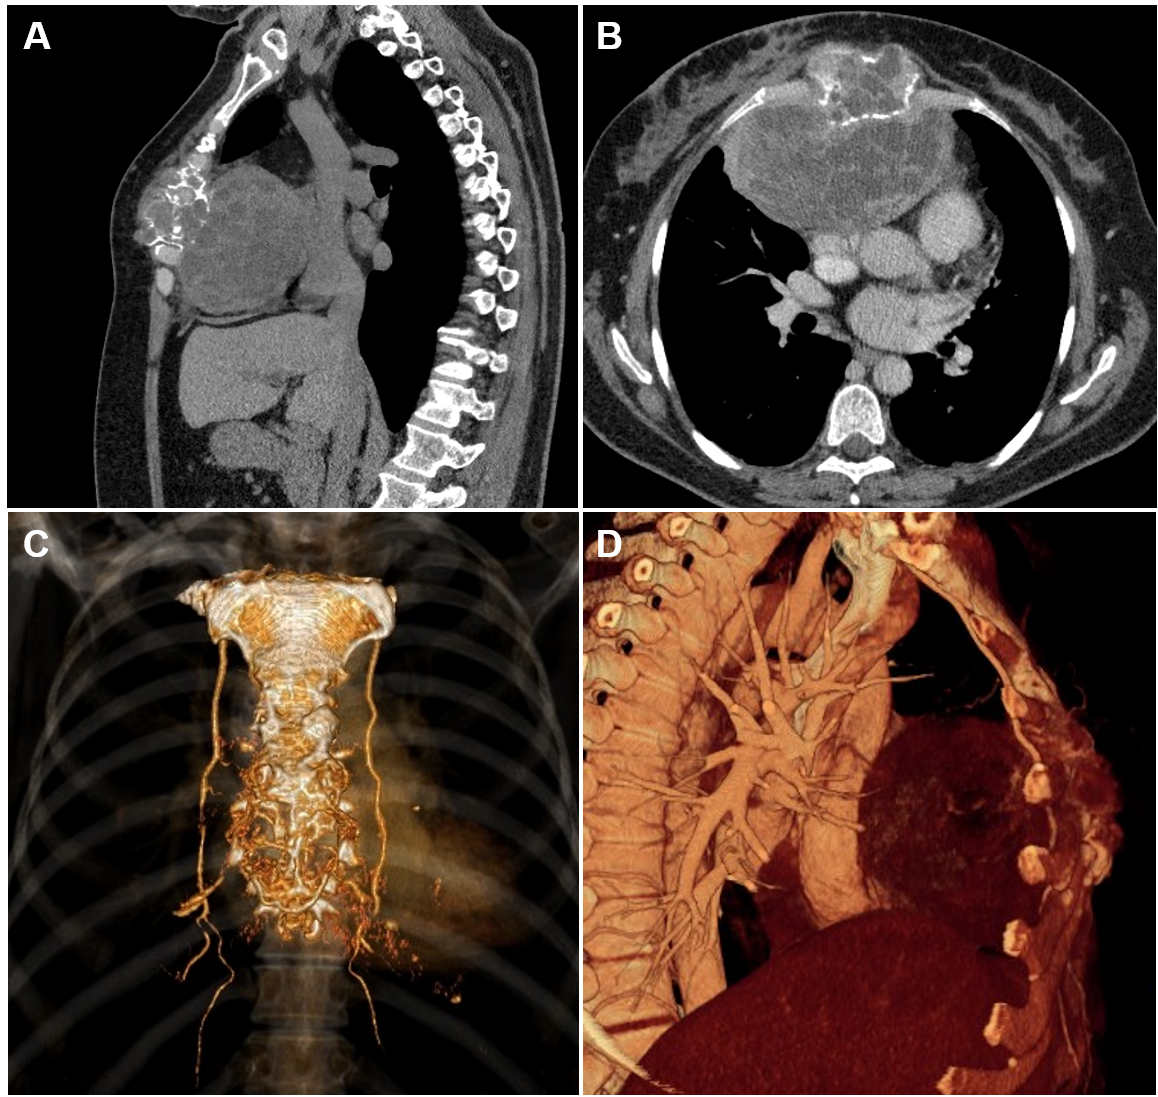

A 50-year-old female with progressive swelling of the anterior chest wall presented with exertional dyspnea, a dry cough, and persistent retrosternal chest pain developing over the course of a year. Physical examination revealed a round, fixed, non‐tender 8x10cm dense mass at the mid-lower aspect of the sternum. The overlying skin was not involved. Laboratory values were normal. A chest computed tomography (CT) revealed a 12.4x9.7 x8.8cm heterogeneous sternal tumor with anterior mediastinal extension. The mass adhered to the mediastinal vascular structures and pericardium, displacing the heart posteriorly and to the left without signs of invasion (Figure 1). Fine-needle aspiration (FNA) cytology was inconclusive. An incisional biopsy established a pathological diagnosis of a sternal giant cell tumor.

Figure 1 (A) Sagittal and (B) axial chest CT images with (C, D) 3-D reconstruction showing large soft-tissue, osteolytic, heterogeneous sternal mass 12.4cmx9.7cmx8.8cm, with direct extension to the anterior mediastinum, supplied by bilateral internal mammary arteries.